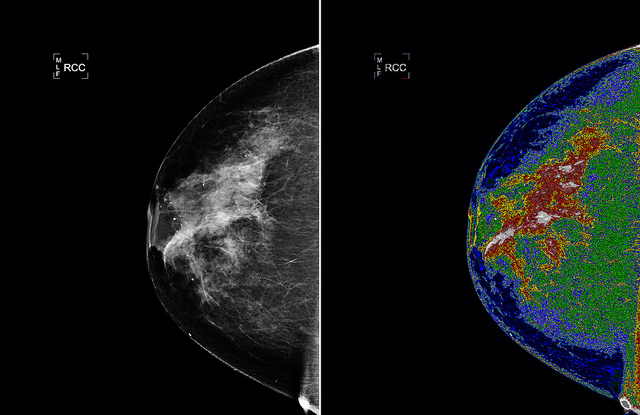

Breast cancer is the most prevalent form of cancer for women worldwide. Current breast cancer clinical practice and treatment mainly relies on the evaluation of the disease’s prognosis using the Bloom-Richardson grading system. The necessary scoring is based on a pathologist’s visual examination of a tissue biopsy specimen under microscope, but different pathologists may assign different grades to the same specimens.

However, the advent of digital pathology and fast digital slide scanners has opened the possibility of automating the prognosis by applying image-processing methods. While this undoubtedly represents progress, image-processing methods have struggled to analyse high-grade breast cancer cells as these cells are often clustered together and have vague boundaries, which makes successful detection extremely challenging.